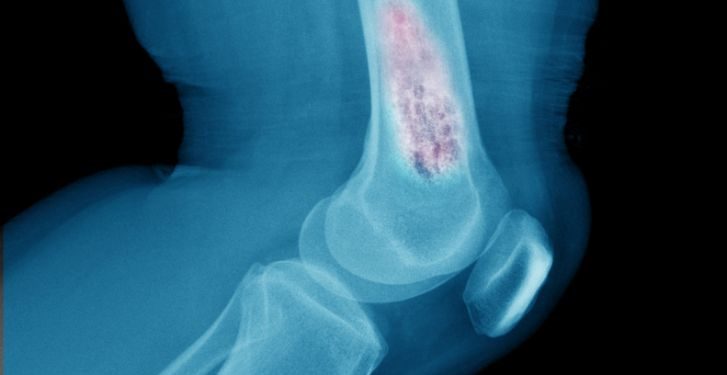

X-rays can show whether a lesion is solid or hollow, and can help identify the type of tumor. A computed tomography (CT) scan or magnetic resonance imaging (MRI) can provide detailed pictures of the bone from many different angles. A dye is injected into the vein before the CT or MRI test to make it easier for doctors to see the structure of the bone and the tumor.

Doctors diagnose bone tumors based on their appearance and symptoms, as well as results from blood tests and imaging tests. They will take a thorough medical history, including details about any previous tumors or cancers that you or your family members have had. Doctors may examine other parts of your body to rule out cancers that can spread to bone, such as lung or skin cancers.